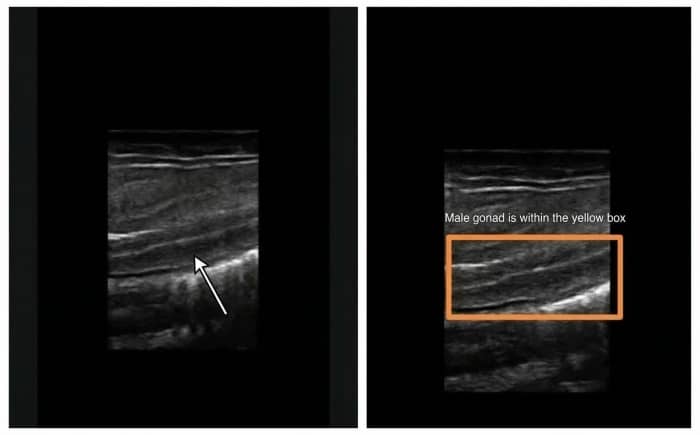

Male gonad ultrasound examination

Female gonad examination